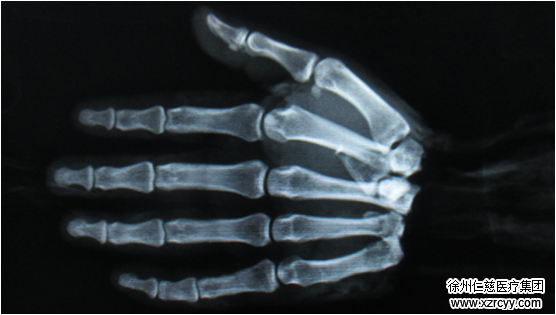

1月11日,48岁的朱师傅在操作除草机时,右手不慎被绞断,手腕出血、断离,右侧远端尺骨骨折。经betway在线登陆3位手外科医生连续8小时的手术,神经、血管、肌腱一一成功吻合,再植成功,断掌“归位”。

郑主任介绍:“患者被送来的时候,右腕自掌腕关节处完全断离,创面创缘不齐,挫伤、污染严重。”高倍显微镜下,郑大伟、吴尧、杨雯三位医护人员联手,将骨折的右侧尺骨复位内固定、将第1掌关节脱位复位内固定,并逐一修复缝合被损伤的神经、血管、肌腱、肌肉、韧带。

整台手术持续8个多小时,在医护人员出色的配合下,高难度的断掌再植手术顺利完成。